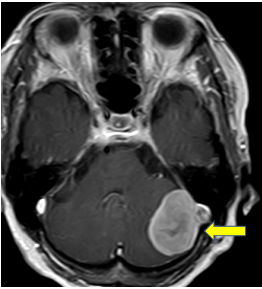

80歳女性 脳腫瘍(髄膜腫)

数年前の検査では見られなかった脳腫瘍が左小脳に発見されました。高齢ですが、急速に大きくなり危険となる可能性があったため、手術を行いました。